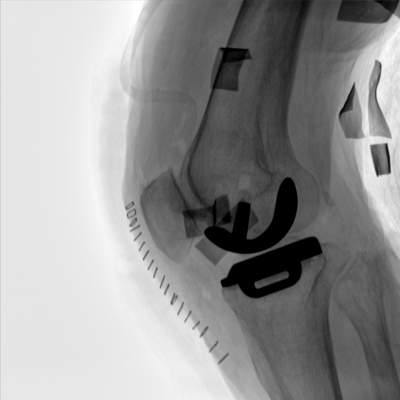

采用智能变频脉冲透视技术,优化图像质量的同时降低辐射剂量,呵护医患健康